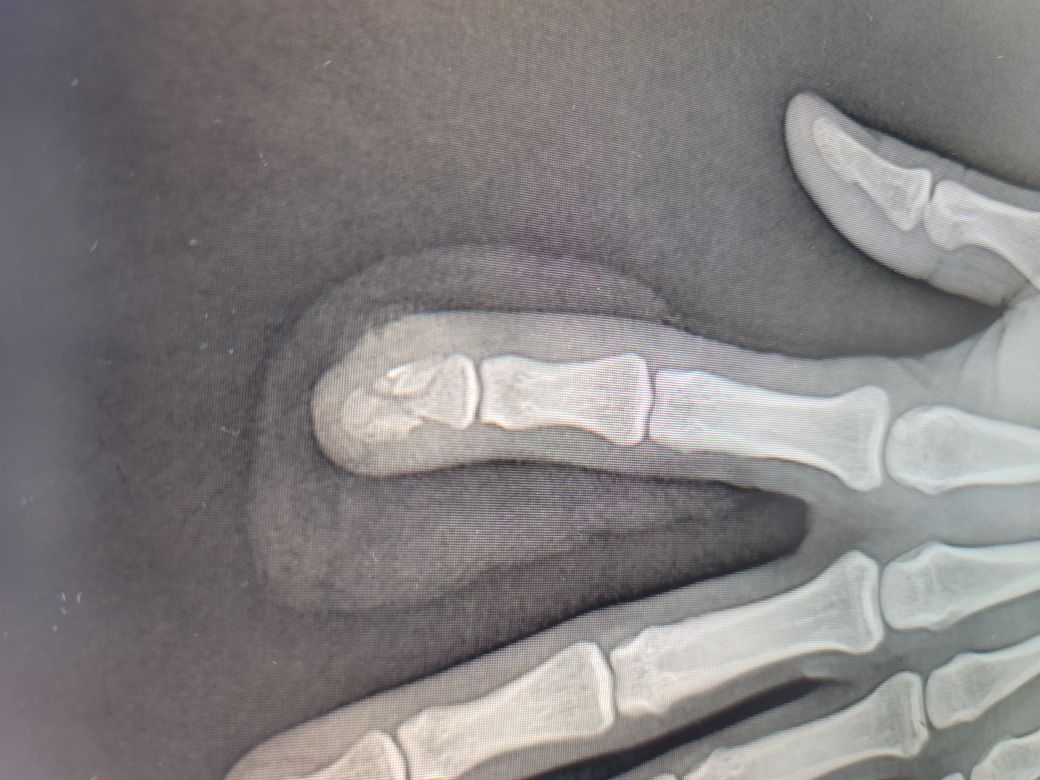

손가락이 관통되고 옆으로 빼면서 찢어진 상처를 봉합수술했습니다 근데 다친 손가락 마디 전체가 피부가 딱딱한게 아니고 피부조직이 단단해진 느낌이고 아직 지문있는 겉피부가 없어서 조금한 자극에도 저릿하고 찌릿한 통증이에요 아직 붓기도 안빠졌으니까 기다리는게 정답일까요 그냥 염증 반응인가요

• 1번 째 사진

• 2번 째 사진

• 3번 째 사진